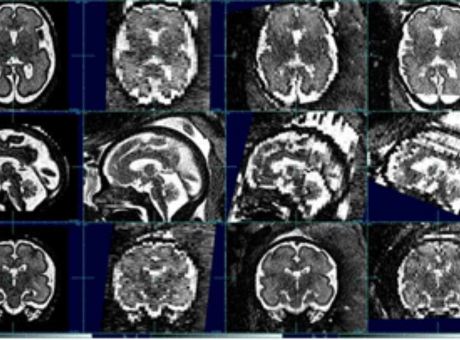

Imaging the fetal brain is challenging as the fetus moves unpredictably during image acquisition resulting in motion degraded images. The lab has created a workflow to create high resolution images from these motion degraded lower resolution images. Additionally, the lab uses these high resolution fetal brain MR images to quantify regional brain volumes, as well as performs placental imaging and quantitative segmentation.

Neonatal brain MRI processing

The lab has expertise in obtaining high quality brain MRI in neonates and young infants without the use of anesthesia using the feed and swaddle technique. Multimodal neonatal and infant brain MR imaging – anatomic, diffusion and BOLD (blood oxygen level dependent) resting state functional MRI are analyzed to understand developmental and functional alterations in the neonatal and infant brain in various conditions. More recently, the lab has investigated infant brain alterations in the setting of prenatal substance exposure.